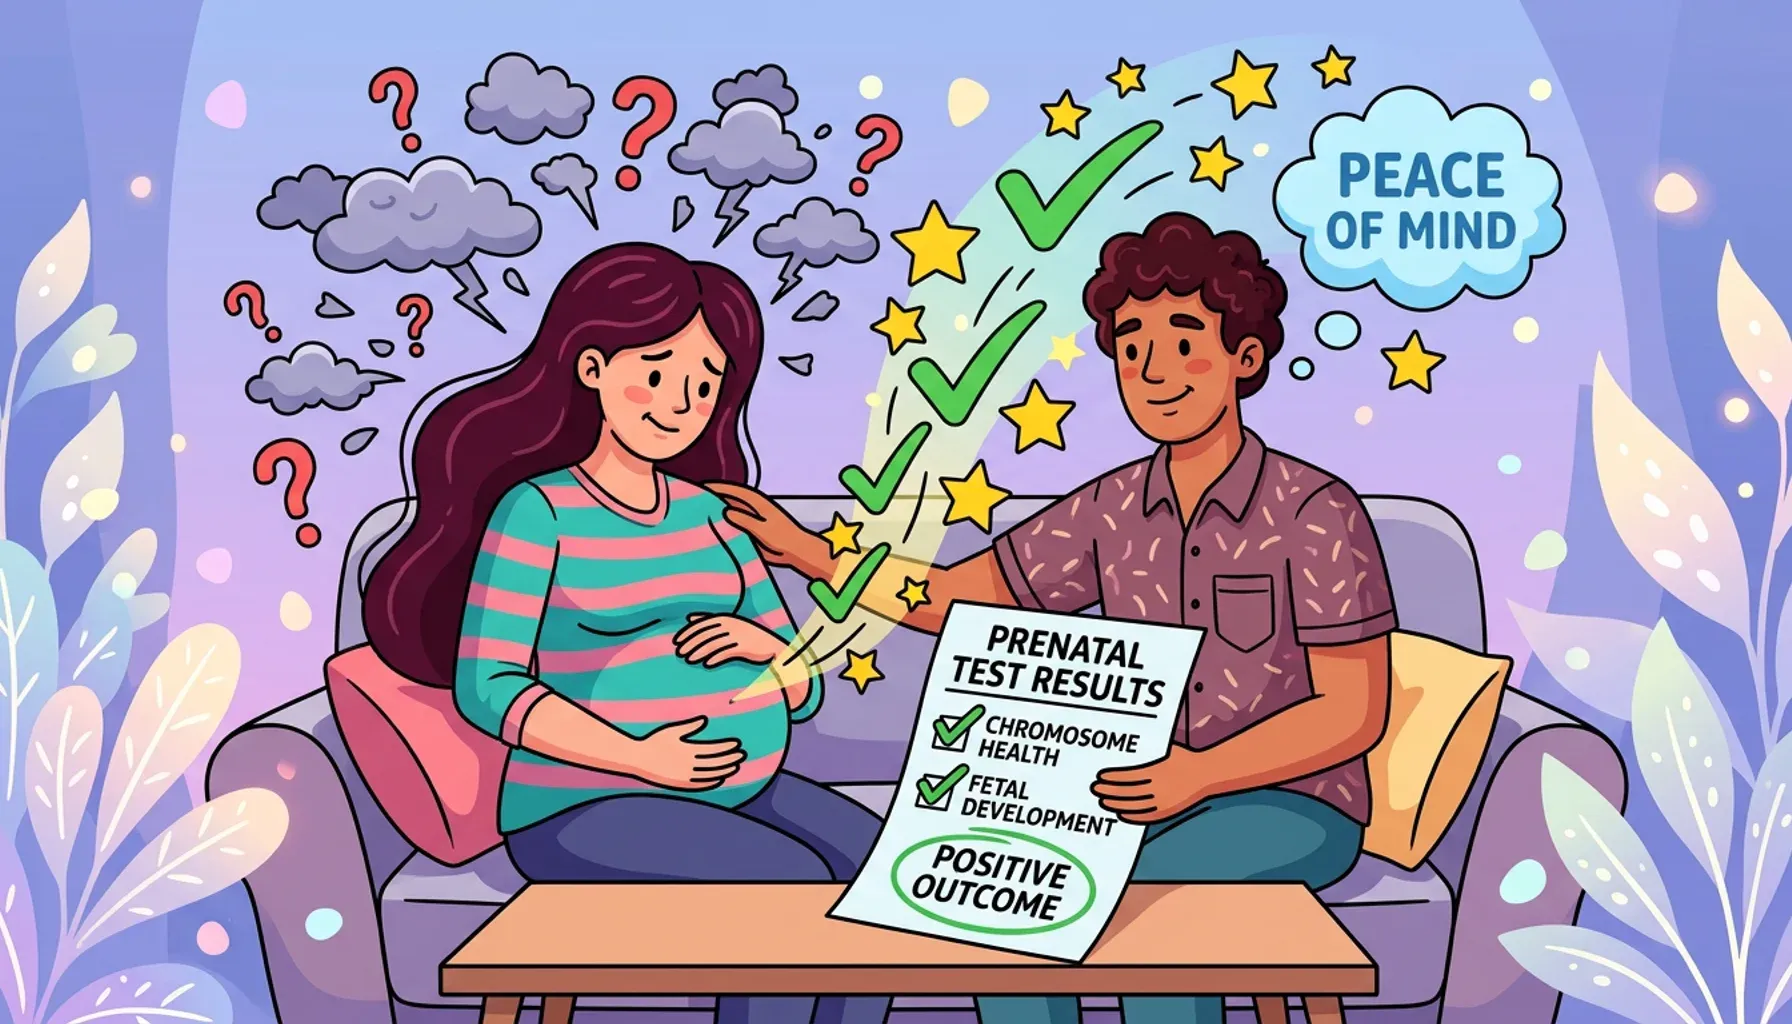

How to overcome fears about the baby

Learn expert strategies to manage pregnancy anxieties and maintain a healthy pregnancy.

How to talk to the doctor during prenatal checks

Master prenatal appointments with expert tips for effective doctor communication.